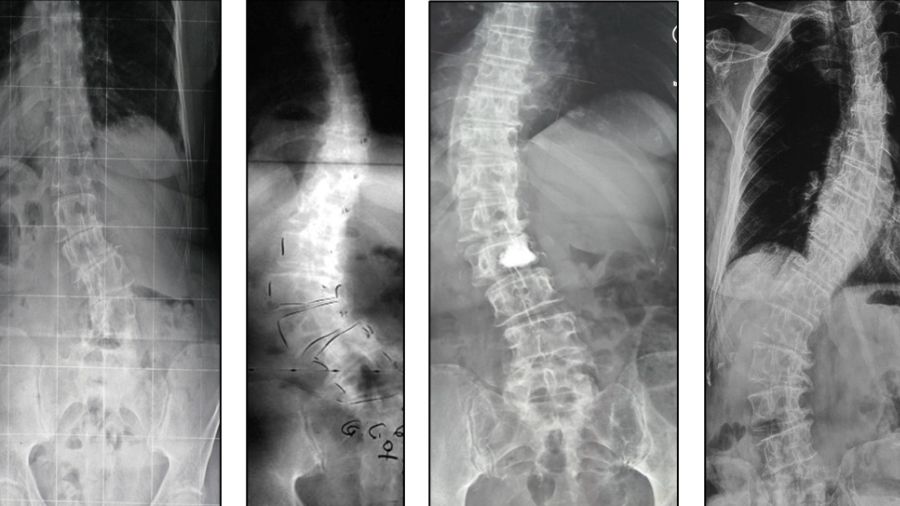

Adult Spinal Deformity (ASD) is not a single disease. It comprises a wide spectrum of pathology and affects up to 30% of the population. The patient population is inherently heterogeneous—not only in the demographics of the patients, the etiology of the condition, but also in the various clinical symptoms and associated comorbidities.

A webinar by Taavi Toomela and Marko Neva covers recognizing adult scoliosis and coronal malalignment patterns, describing spino-pelvic changes in adult deformity, differentiating sagittal malalignment, spinal imbalance, and compensatory mechanisms in adult deformity, and acknowledging HRQoL parameters and age specific thresholds in adult scoliosis. It features the use of the AO Spine ASD Patient Profile.

Antonio Faundez describes evaluation and principles of surgical strategies for ASD, including general principles, pathomechanism, importance of clinical and radiological evaluation, and potential complications, such as proximal junctional kyphosis.